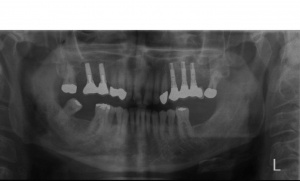

Der Erstbefund zeigte eine generalisiert entzündliche marginale Gingiva mit generalisierter Blutungsneigung bei Sondierung. Die approximalen Sondiertiefen waren durchgehend erhöht und betrugen im Molarenbereich bis zu 12 mm (s. Abb. 4). Es lagen multiple Zahnlockerungen vor, eine Zahnlockerung des Grades II zeigte sich an den Zähnen 11, 25, 26, 38, 37, 47; Grad III am Zahn 24. Harte Beläge in der Unterkieferfront, generalisiert weiche Beläge (API 62 %). Wurzelkaries an 24. Suffiziente Brückenversorgung im I. Quadranten. Die Panoramaschichtaufnahme von Juni 1998 (s. Abb. 4) zeigt einen generalisierten horizontalen Knochenabbau mit vertikalen Einbrüchen in regio 17, 25, 37 und 47. Interradikuläre Aufhellungen im Sinne einer Furkationsbeteiligung an 17, 26, 38, 37 und 47. Via falsa an 24.

a) Initialbehandlung vom 18.06.1998 – 27.10. 1998:

Gemäß den Vorgaben einer systematischen Parodontalbehandlung wurden zunächst mehrfache professionelle Zahnreinigungen mit Anleitung des Patienten zu einer effizienten häuslichen Mundhygiene durchgeführt. Hierbei konnte der SBI auf 15 %, der API auf 8 % gesenkt werden. Nach Abschluss der Initialtherapie im Oktober 1998 wurde ein entsprechender Parodontalstatus (s. Abb. 5) erstellt und mit dem Patienten der weitere Behandlungsablauf besprochen. Aufgrund der fortgeschrittenen parodontalen Destruktion musste eine Vielzahl von Zähnen als prognostisch fragwürdig beurteilt werden. Die Prämisse der Behandlung war jedoch, den Patient sowohl kurz- als auch langfristig möglichst mit einem festsitzenden Zahnersatz zu versorgen. Als nicht erhaltungswürdig wurden die Zähnen 24, 25, 37, 38 und 47 beurteilt.